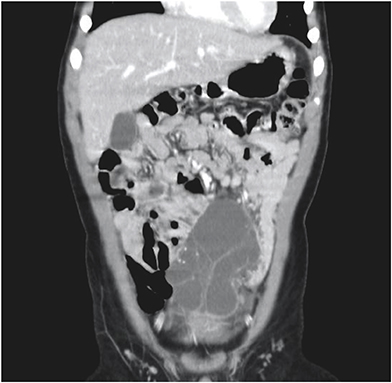

All patients underwent abdominal ultrasonography and computed tomography (CT) scans. In patient No. 7, these modalities showed a cystic mass, 9 cm in size, with multiple septa in the lower abdomen (Figs. 1, 2). An abdominal CT scan of patient No. 9 showed a huge multiloculated cystic mass with a septum; this mass occupied nearly the entire abdominal cavity and caused the displacement of the bowel to the left posterior abdomen.

Fig. 4

Photograph of the huge retroperitoneal multicystic mass removed from patient No. 9. The mass was attached to the ascending colon and cecum and extended from the retrocecal region medially to the root of the small bowel mesentery, superiorly to the paraduodenal space level and inferiorly to the level of the pelvic inlet.